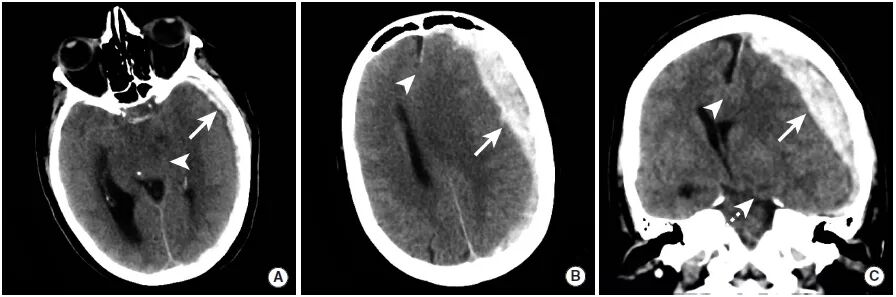

图3

为了清楚地看到病变,CT的窗宽窗位做了一些调整。与硬膜下窗(图C、D)相比,病变在标准脑窗(图A、B)上不太明显。图中可见右前颞叶出血性挫伤和覆盖脑沟的蛛网膜下腔出血(三角箭头),骨板下可见弧形硬膜下血肿灶(长尾箭头)。